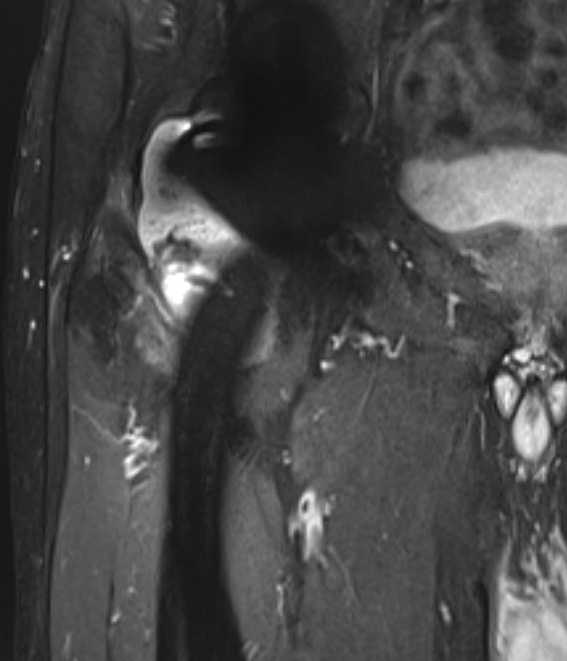

Adverse Local Tissue Reactions (ALTR)

Mechanism

Generation of biologically active, nanometer sized metal particles

- cause large inflammatory reaction

- pseudotumour (AKA aseptic lymphocyte-dominant vasculitis associated lesion ALVAL)

- can cause extensive soft tissue and bone loss

Diagnosis

Pain

High serum ion levels

Loosening on xray

Pseudotumour on MRI